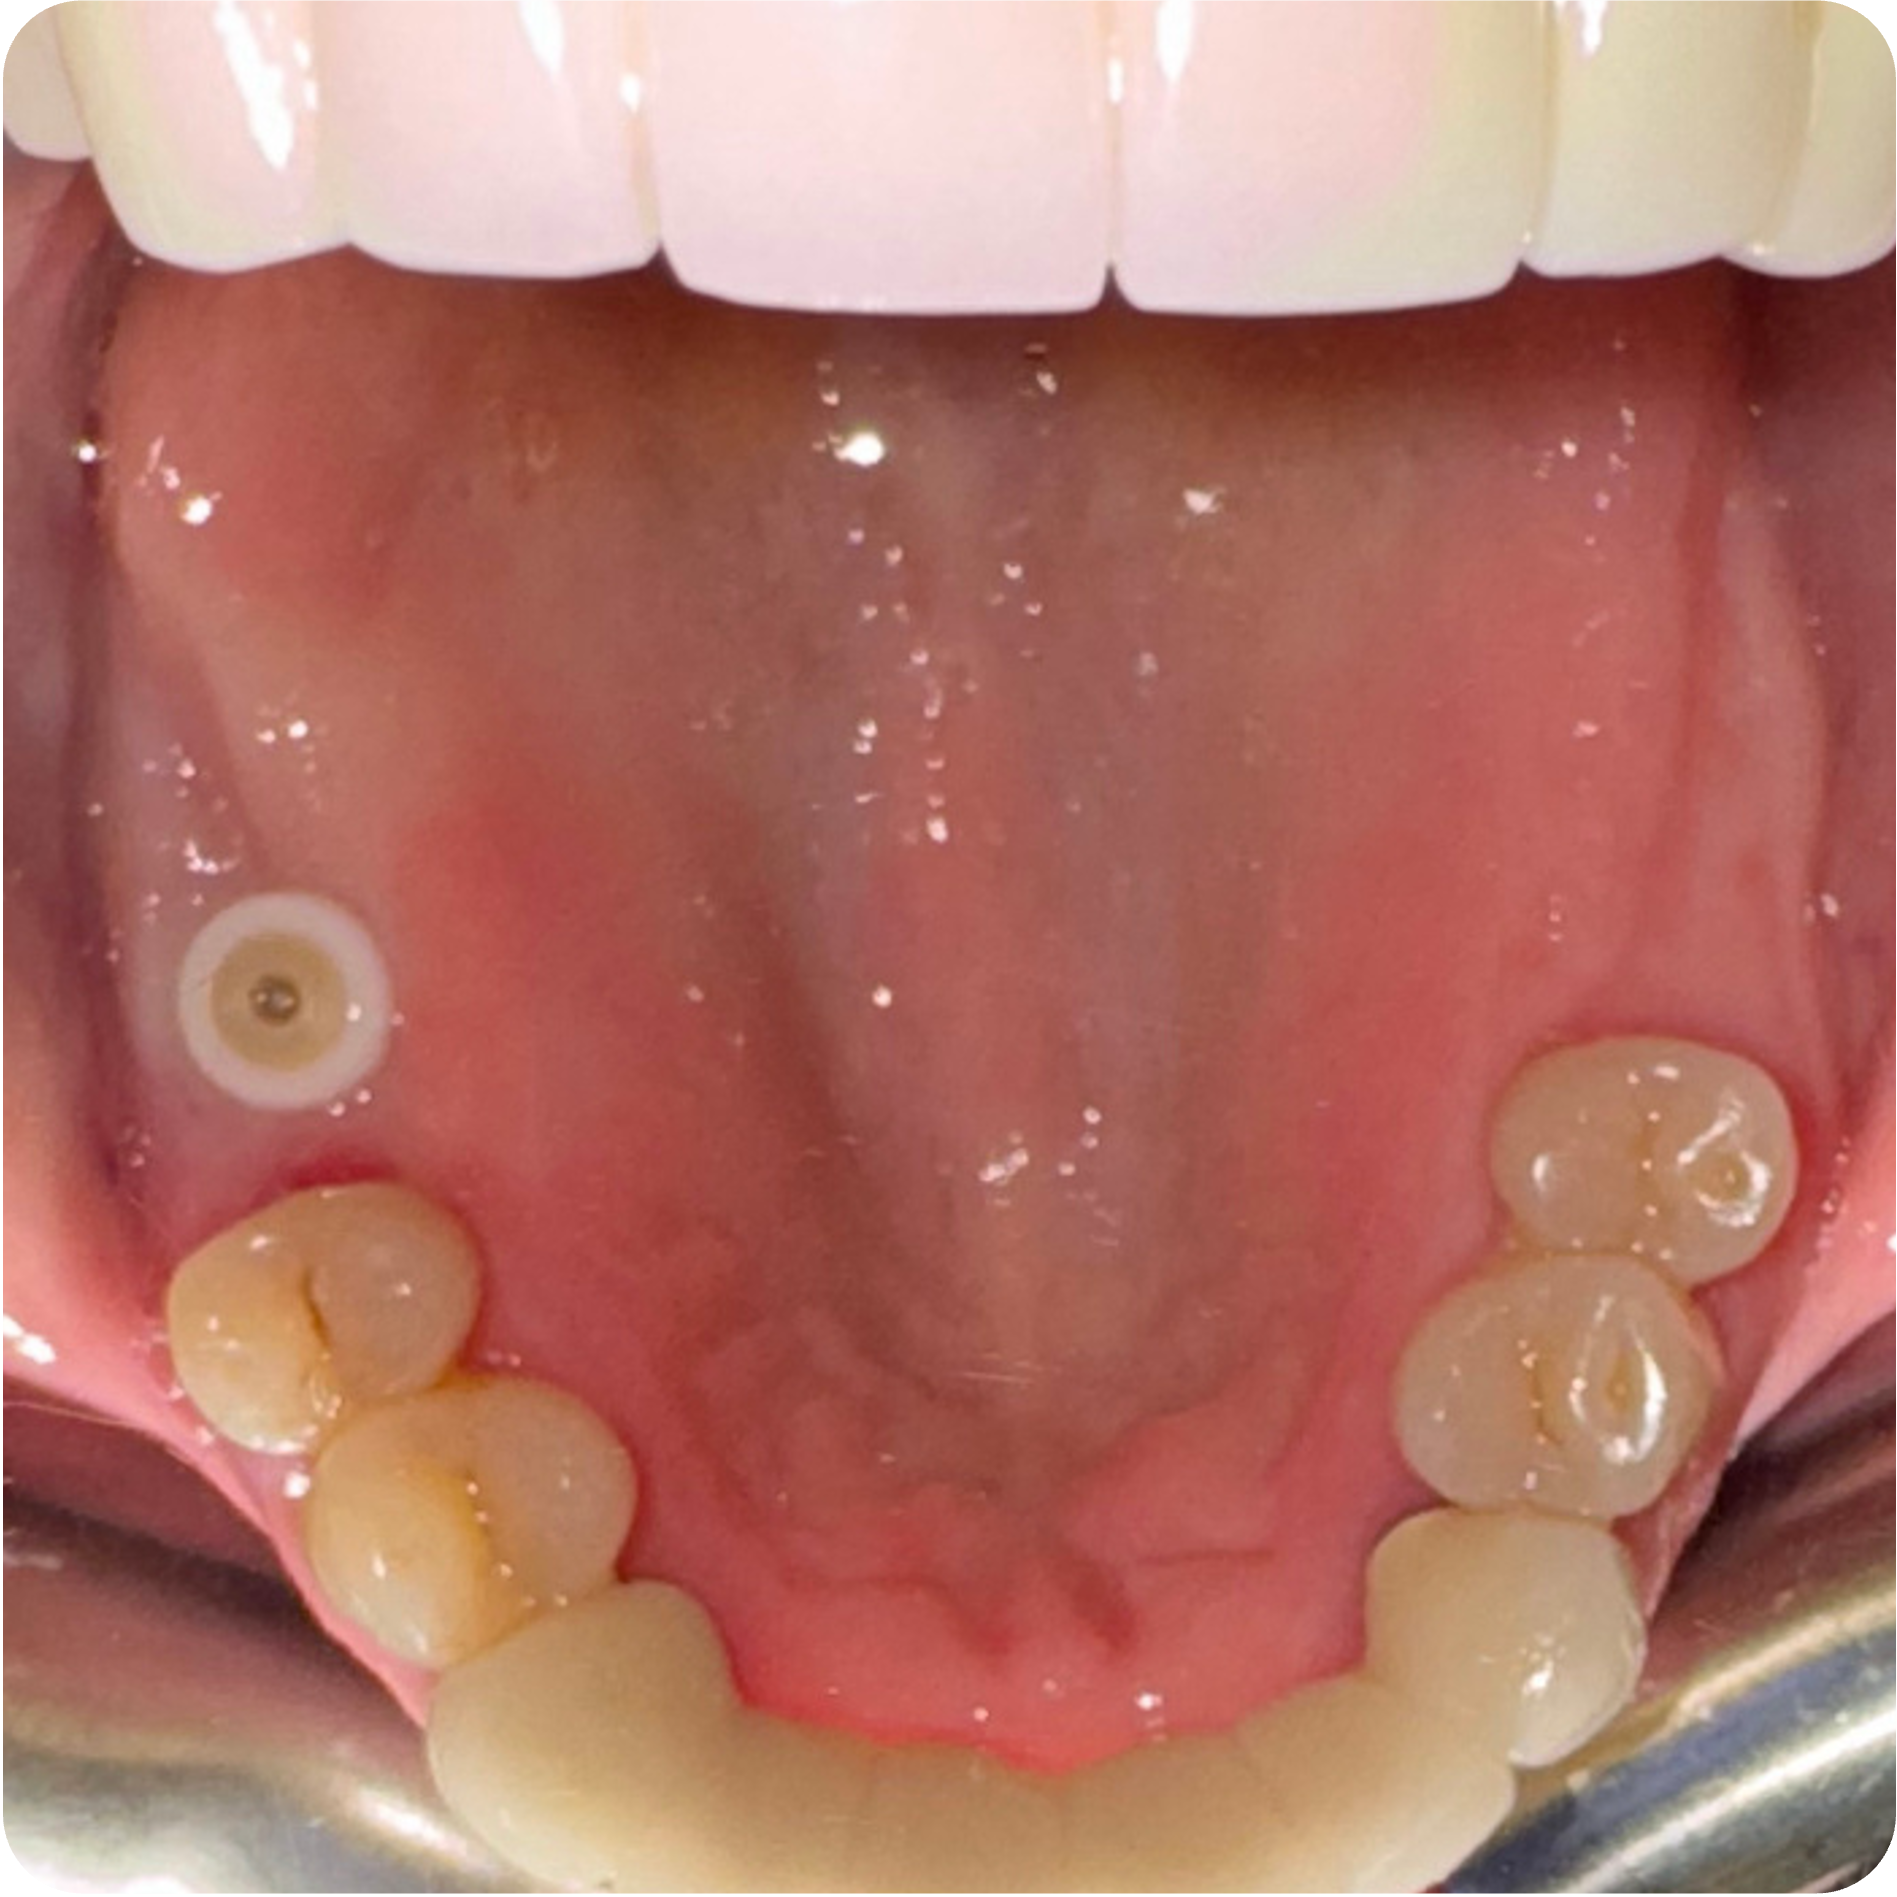

Visual Case Progression

All clinical images are shown at a consistent size for easy comparison.

Before & After (Groton Wellness Perio Protocol)